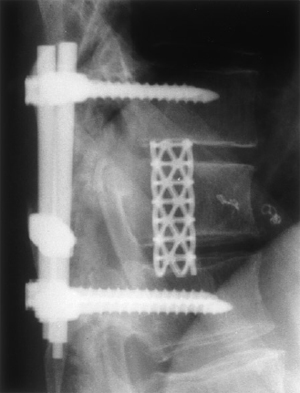

A costotransversectomy was performed and tumour encountered at the posterior aspect of the pedicle. Tumour removal was carried out until the pedicle was removed and a clear corridor available for introduction of the endoscope via a lateral approach (Fig. 3). Tumour removal under endoscope assisted control was accomplished with the aid of curettes and bipolar diathermy until a compete macroscopic clearance achieved. A Pyramesh titanium cage (Soframor-Danek) was packed with bone graft and impacted into the defect between T10±T12 for anterior column stabilization (Fig. 4). Methylmethacrylate was also inserted into the dead space arround the cage. Fixed angle pedicle screws (HorizonTM Soframor-Danek) were inserted into T10 and T12 with rods

Fig. 4 Postop lateral X-ray: anterior and posterior column stabilization.